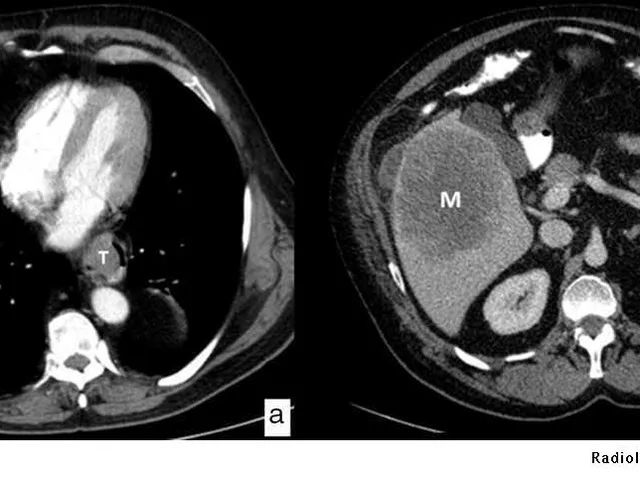

- Learn to perform a methodological and standardised reading of the CT and MRI scan images for oesophageal-gastric cancer.

- Recognise the imaging date and assess the staging of oesophageal-gastric cancer.

- Learn to identify the relevant local anatomy in order to adequately simulate and plan the radiation therapy for oesophageal-gastric cancer.